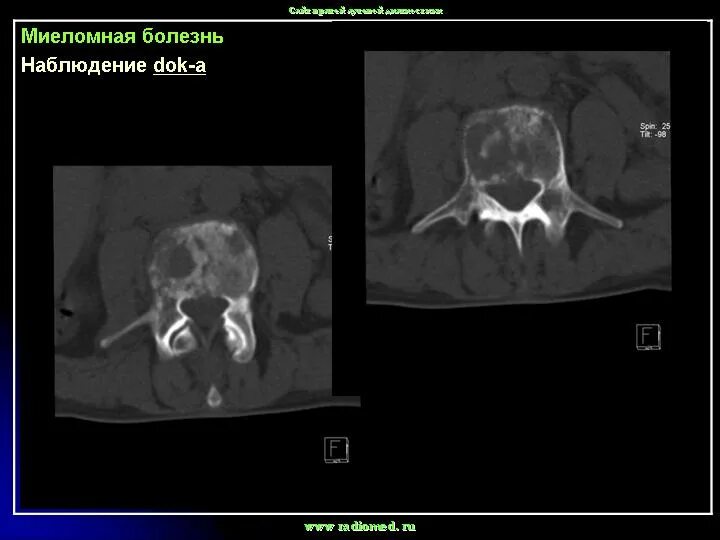

Заболевание кт